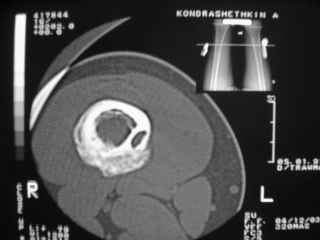

Здравствуйте, уважаемые коллеги!Представляю вашему вниманию интересный случай и пока что непонятный для меня в диагностическом плане. На днях в наше отделение (детской ортопедии и травматологии) поступил 13-летний мальчик по направлению из поликлиники с диагнозом: остеома нижней трети правого бедра.

Анамнез практически никакой: в следствие травмы (растяжение связок коленного сустава) от 07.11.2004 выполнены Rg-граммы в травмпункте и обнаружено опухолевидное образование. Первичные Rg-граммы я не публикую, так как они заметно худшего качества, да и динамики за прошедшие три недели не отражают. Болевой синдром купирован в течение трёх дней. В настоящий момент мальчика ничего не беспокоит. Ходьба не нарушена, опухоль пальпируется с трудом по задней поверхности в н\3 правого бедра, пальпация безболезненна, объем движений в суставах правой нижней конечности полный и симметричный. Кожа над опухолью не изменена.В нашей клинике проведено дополнительное обследование: общие анализы крови и мочи, биохимия крови без особенностей. Выполнены Rg-граммы на цифровом Siemens обычные и продольные томограммы срезами 3-5 мм, а также компьютерная томография поперечными срезами по 5 мм. Прошу обратить внимание, что на приведённых томограммах видны две полости 10х15 мм и 15х60 мм. Также имеются два опухолевидных образований наслаивающихся друг на друга: уплощённое и вытянутое 10х100 мм и элипсовидной формы 15х30 мм. Это хорошо заметно на фото a_1.jpg c_1.jpg и d_1.jpg. Плотность внутри полостей 125% от плотности костномозгового канала, плотность наружного опухолевидного образования 55% от плотности кортикального слоя. Также отмечается линия перелома по центру наружного опухолевидного образования.Исходя из полученных данных мнения в плане диагноза несколько разделились от 1)сочетания кортикальной фиброзной дисплазии и латентно протекавшего маршевого перелома н\3 правого бедра до 2)остеосаркомы. В отношении первого варианта не сходится отсутствие клиники при переломе такой крупной кости как бедро, второй вариант вообще оставлю без комментария, ибо некомпетентен. Хотелось бы услышать мнения коллег, с удовольствием ознакомлюсь с любыми предположениями и замечаниями.С уважением, Александр Е. КлоковОтделение детской ортопедии и травматологииБСМП г. Мурманска.